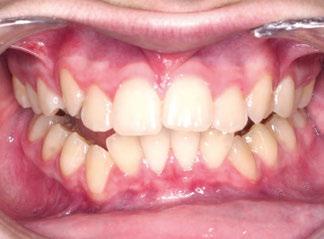

La niña de las figuras 1 a 3 presenta una leve asimetría facial con patrón braquifacial por tercio inferior disminuido y mentón desviado ligeramente hacia la derecha; los labios son competentes y en sonrisa apenas se exponen los incisivos. El perfil es excesivamente convexo,

con escasa proyección del mentón, y con los ángulos de la convexidad (155 º) y mentolabial (70 º) disminuidos y el nasolabial (103 º) en norma.

La exploración intraoral (figuras 4 a 8) revela una Clase II molar y canina completa, líneas 1/2 dentarias superior 0,5 mm e inferior 1 mm ambas desviadas hacia la derecha, los incisivos superiores excesivamente protruidos y vestibulizados (seguramente debido a la interposición del labio inferior), resalte de 13 mm y sobremordida 2/3 de corona. La discrepancia oseodentaria

inferior es de -3,5 mm y la curva de Spee de 4 mm.